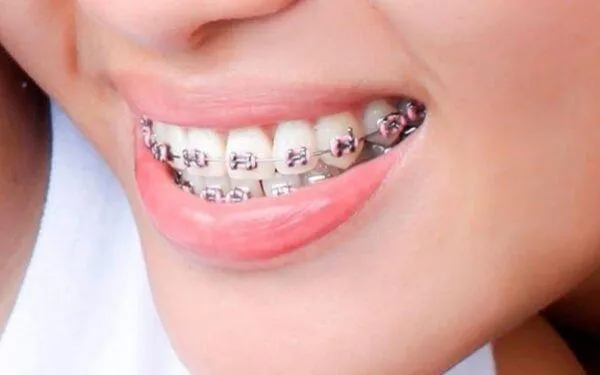

Niềng răng là một phương pháp chỉnh nha phổ biến, giúp điều chỉnh vị trí răng mọc lệch, khấp khểnh về đúng vị trí trên cung hàm.